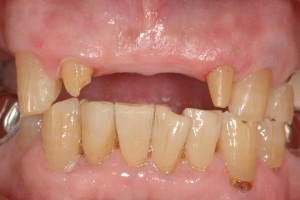

まずは、術前と術後の比較から見てみてください。

左が術前写真です。歯茎が痩せていて虫歯になっています。こういう場合、単に削って白い樹脂を詰めるでしょうか?

このケースのように歯茎が薄い場合(付着歯肉の厚みがなく狭い)、白い樹脂を詰めてもまた歯茎が痩せていくことが予想されます。

右は、術後写真ですが、白い樹脂は詰めていません。歯茎を作って、虫歯の部分を完全に覆いました。